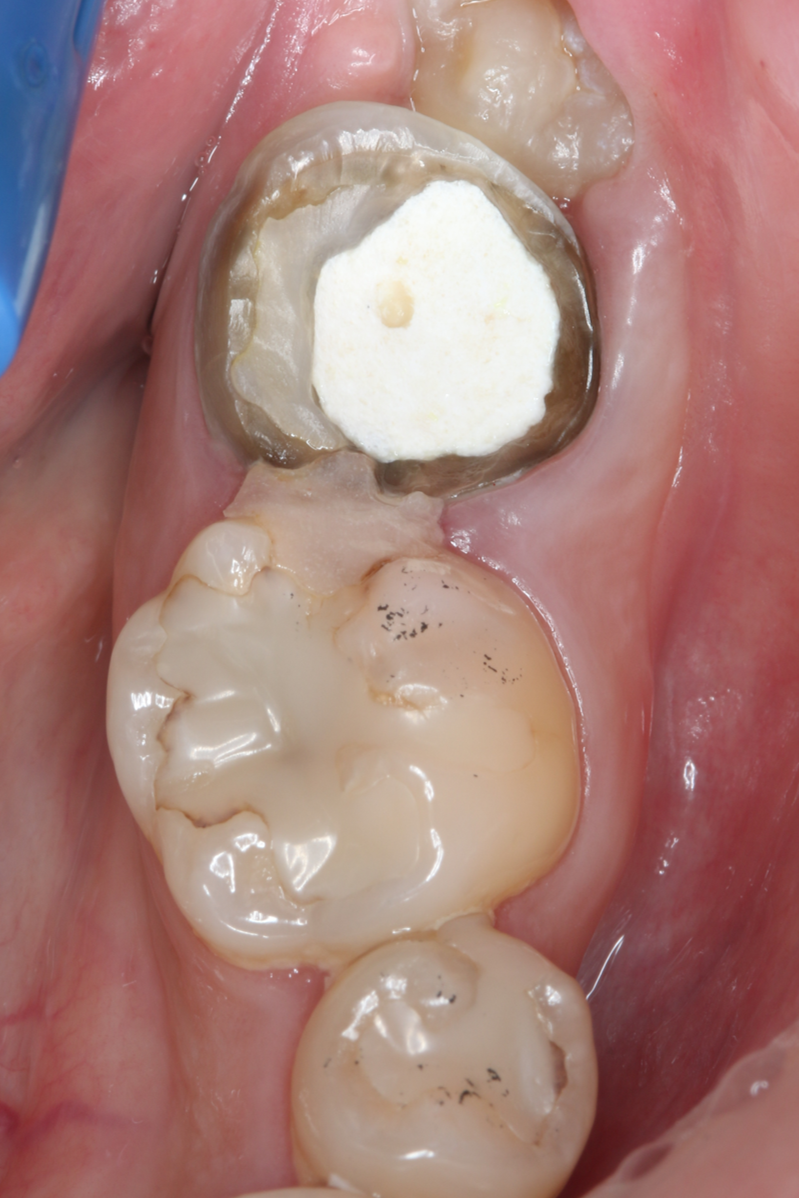

症例2

| 患者様データ | 40代 男性 |

| 来院時の主訴 | 「左下が痛くて噛めない。」 |

| 医院の診断 | 左下第一大臼歯歯根破折、慢性根尖性歯周炎 |

| 通院期間 | 6か月 |

| 来院回数 | 9回 |

| 治療費 | 総額:275,000円(税抜) 【内訳】 歯牙移植150,000円、ファイバーポストコア20,000円、セラミック治療85,000円、歯頸部ダイレクトボンディング10,000円×2 |

| リスクと副作用 | ①根管治療歯は長期的には破折するリスク ②長期的なメインテナンスが必要 ③歯根の外部吸収 |

| ここがこだわりのポイント!☝ |

抜歯が必要になった際に余っている親知らずがあれば移植歯として利用することができます。 術前に撮影したCT画像から3Dプリンターを用いて親知らずのレプリカを作製することで、親知らずが乾燥することを防ぎ、成功率が上がるよう努力しています。 |